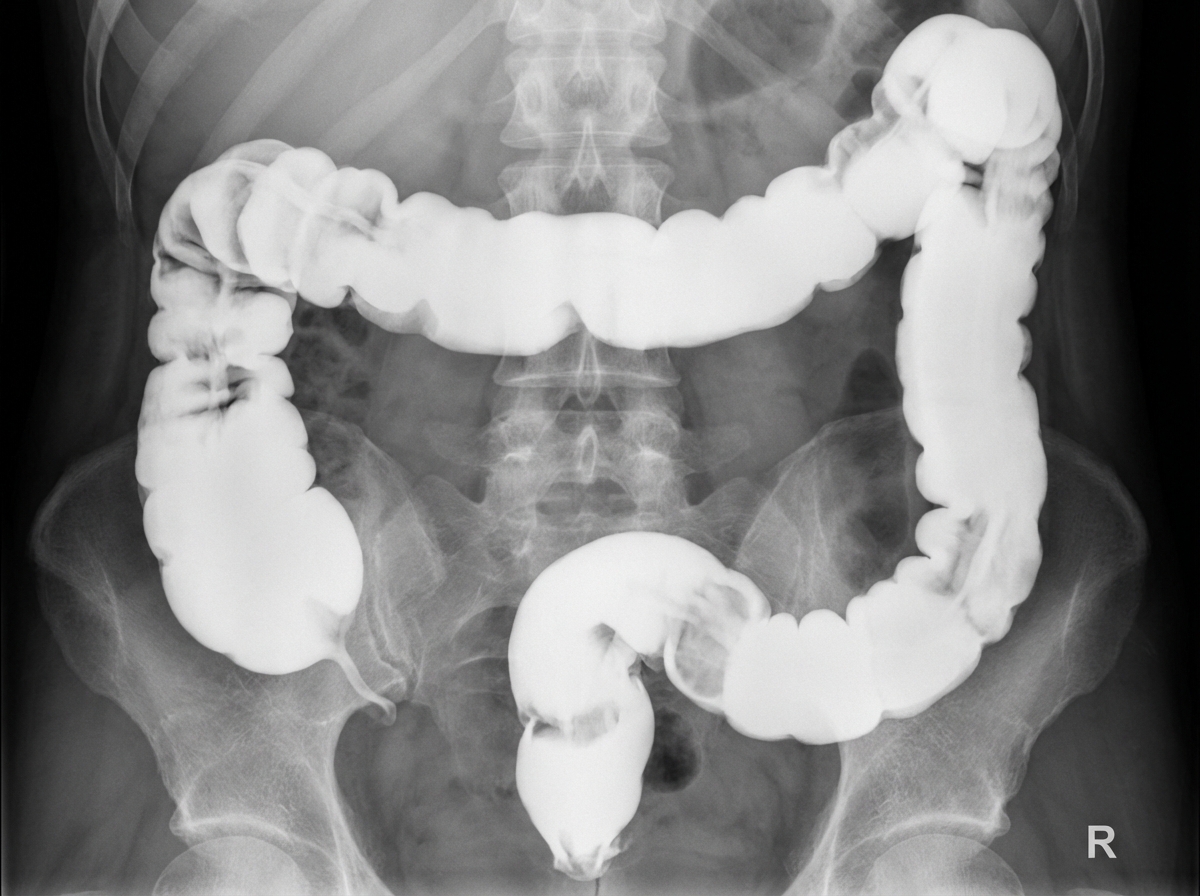

What condition is suggested by the below X-ray?

Explanation: ***Ulcerative colitis*** - X-ray shows classic **lead pipe colon** appearance with **loss of haustrations** and smooth, featureless bowel wall typical of ulcerative colitis. - Demonstrates **continuous involvement** from the rectum extending proximally, which is characteristic of ulcerative colitis. *Carcinoma colon* - Typically presents with **apple-core lesion** on barium enema showing circumferential narrowing with abrupt margins. - Shows **localized stricture** rather than the diffuse smooth appearance seen in this X-ray. *Crohn's disease* - Characterized by **skip lesions** with areas of normal bowel between affected segments, not continuous involvement. - Shows **cobblestone appearance** with deep ulcerations and **transmural inflammation**, contrasting with the smooth appearance here. *Whipple's disease* - Primarily affects the **small bowel**, not the colon, so would not produce these colonic X-ray findings. - Associated with **PAS-positive macrophages** and systemic symptoms like **arthritis** and **neurological manifestations**.